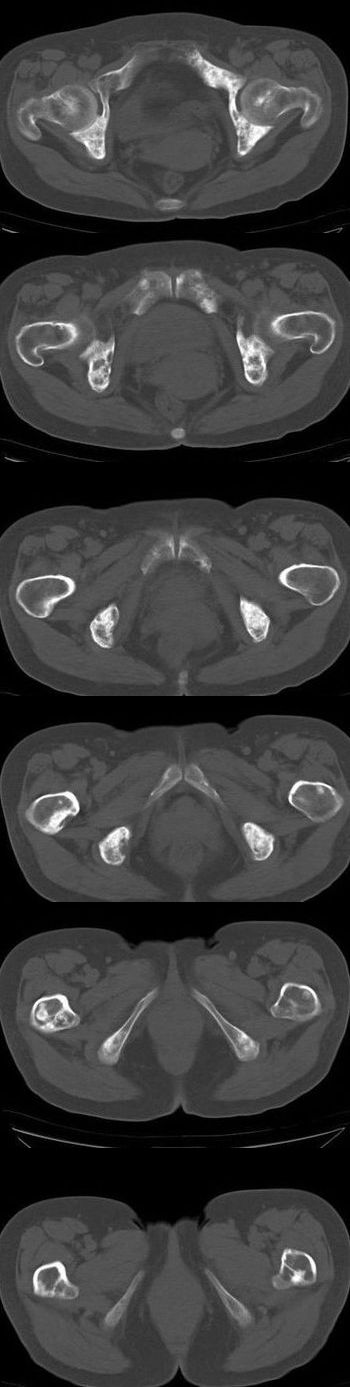

女,54岁。乳腺癌术后8年。现感觉左腿酸困不适,并向下放散。左腿僵硬,不由自主。

典型溶骨型转移瘤。

骨盆及腰椎多发性溶骨性转移瘤.

成骨及融骨转移。

结合病史考虑乳腺癌术后多骨骨转移。

患者臀部皮下脂肪、筋膜、臀大肌处多个小结节、钙化影,看来挨了不少肌肉注射的苦头

支持 骨转移瘤---混合型以溶骨为主

结合临床考虑多骨多灶性溶、成骨性转移。